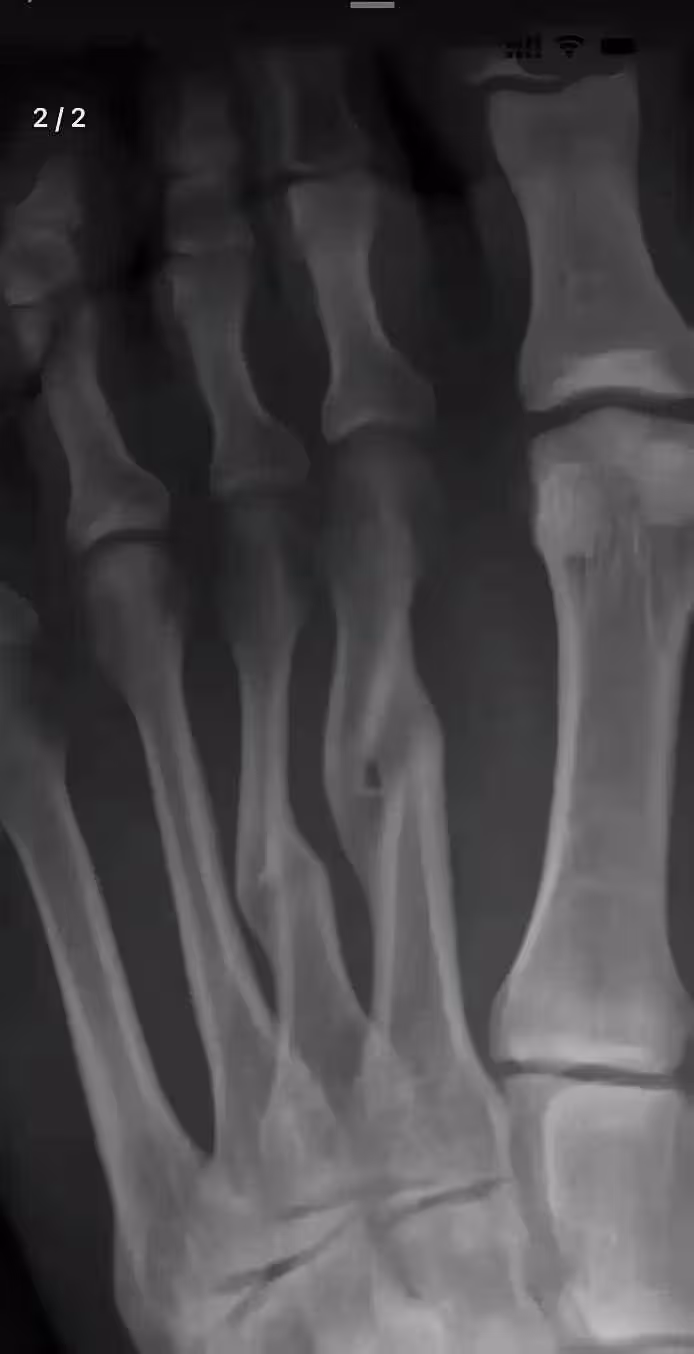

直到複查那天,新的X光片讓所有人都愣住了——原本錯位的斷骨,竟在未手術的情況下,奇蹟般地長合在一起了。

「這……」醫生推了推眼鏡,仔細比對著新舊兩張片子,「雖然癒合處有輕微隆起,關節面也略顯不平,但確實自然癒合了。

」他指著片子解釋:「人體骨骼本身就有強大的自愈能力,手術的鋼釘鋼板只是幫助復位,真正讓骨頭連線的,還是身體自身的成骨細胞。